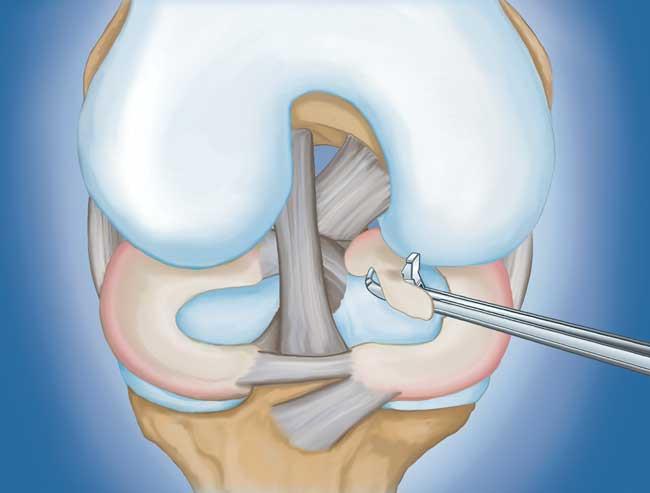

• 半月板修復。  一些半月板撕裂可以通過(guò)將撕裂的碎片縫合(縫合)在一起來(lái)修復。撕裂能否成功修復取決于撕裂的類(lèi)型,以及受傷半月板的整體狀況。因為半月板必須一起愈合,修復的恢復時(shí)間比半月板切除術(shù)長(cháng)。

部分半月板切除術(shù)特寫(xiě)

用縫線(xiàn)修復撕裂的半月板